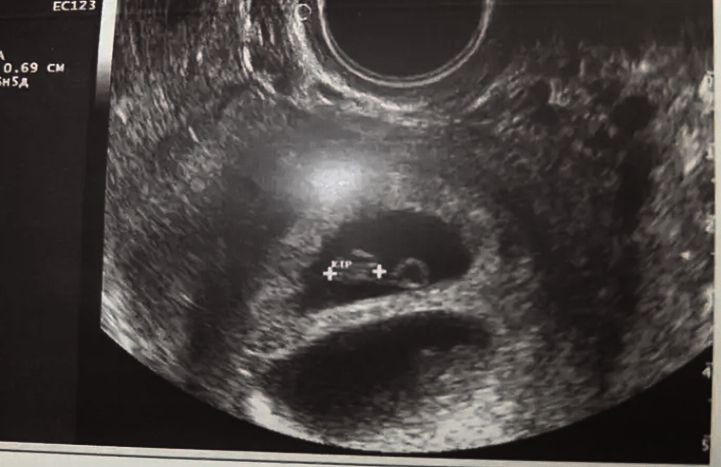

У меня дочь в тазовом предлежании до сих пор

Срок 35 недель . Врач сказала что не страшно будем рожать сами если правильное положение ног , если не правильное то да кесарево . Переворот доделать не будет - опасно , может быть отслойка .